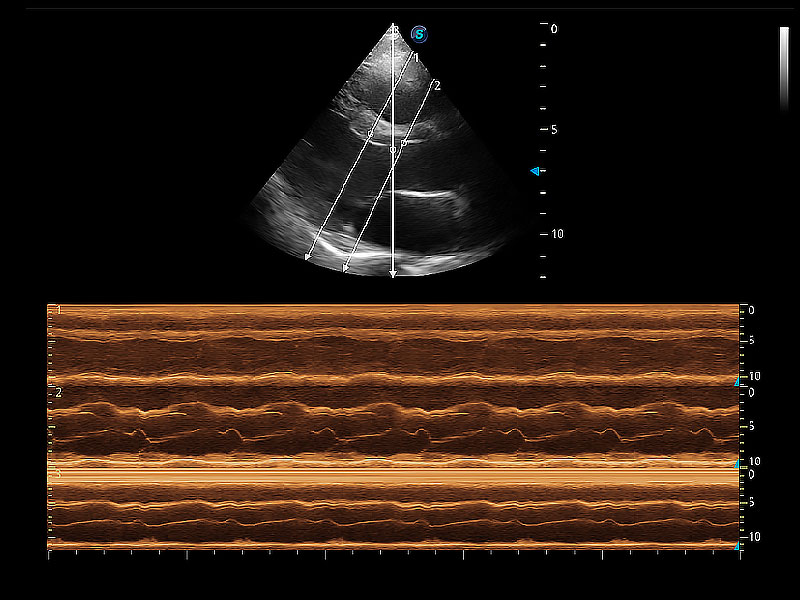

ProPet 80 配備了豐富的心臟探頭群、先進(jìn)的成像技術(shù)和專業(yè)的心臟測(cè)量工具,可幫助動(dòng)物醫(yī)生為不同體型和生理結(jié)構(gòu)的動(dòng)物提供心臟和心肌功能的全面評(píng)估。

通過(guò)360度任意調(diào)節(jié)3條M型取樣線,在同一心動(dòng)周期上觀察心臟不同位置的運(yùn)動(dòng)曲線,得到準(zhǔn)確的心功能測(cè)量數(shù)據(jù),有效評(píng)估心肌運(yùn)動(dòng)及左心室功能。